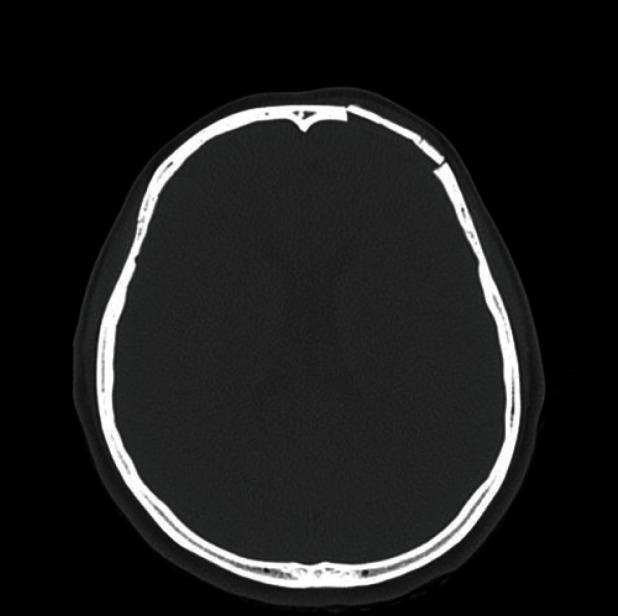

Primary intraosseous hemangioma in the frontal bone.

Primary intraosseous hemangioma in the frontal bone.额骨原发性骨内血管瘤